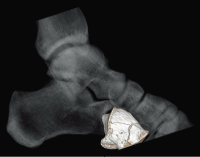

Клинические изображения

Специальная программа HIMAR для подавления влияния на изображения включений с большим КТ числом даёт возможность визуализировать области и ткани, прилежащие к металлическим объектам, например имплантам.